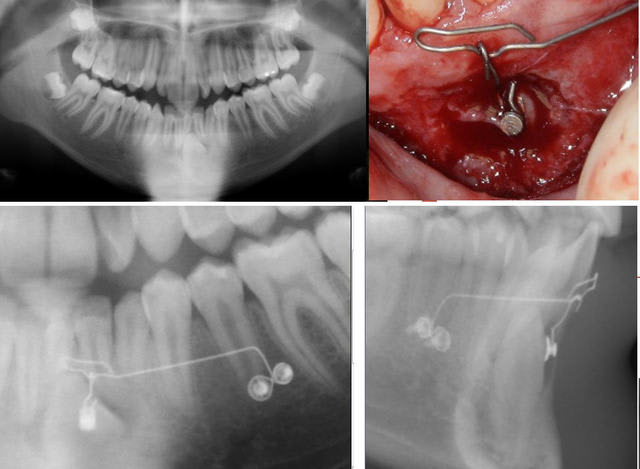

Suite et fin de la première série, voici le coupable :

Test canines suite et fin ndz0su - Eugenol

Test canines 10 olvdlx - Eugenol

Test canines fin t89kvx - Eugenol

Voici une photo per-op où on voit parfaitement sa situation. C’est la première photo faite, j’avais d’abord fixé une ligature, puis l’ai remplacée par un TMA pour pouvoir exercer un bras de levier vestibulaire.

Le téléprofil ici est trompeur, car on n’individualise pas bien les incisives.